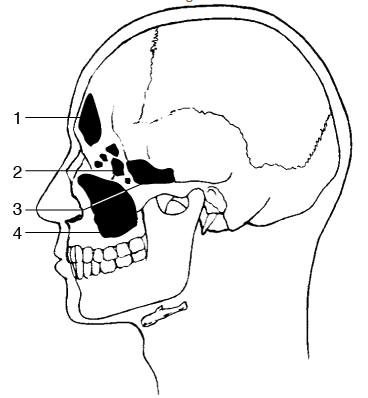

The figure illustrates an anatomic lateral view of the paranasal sinuses. Number 1 points to the frontal sinuses and number 2 to the ethmoidal sinuses; both can be visualized using the PA axial projection (Caldwell method). Number 3 is the sphenoidal sinuses, which are well demonstrated in the SMV projection. Number 4 is the maxillary sinuses, which are best demonstrated using the parietoacanthial projection (Waters method). The lateral projection demonstrates the four pairs of paranasal sinuses superimposed on each other.

Figure 2–14 illustrates an anatomic lateral view of the paranasal sinuses. Number 1 points to the frontal sinuses and number 2 to the ethmoidal sinuses; both can be visualized using the PA axial projection (Caldwell method). Number 3 is the sphenoidal sinuses, which are well demonstrated in the SMV projection. Number 4 is the maxillary sinuses, which are best demonstrated using the parietoacanthial projection (Waters method). The lateral projection demonstrates the four pairs of paranasal sinuses superimposed on each other.